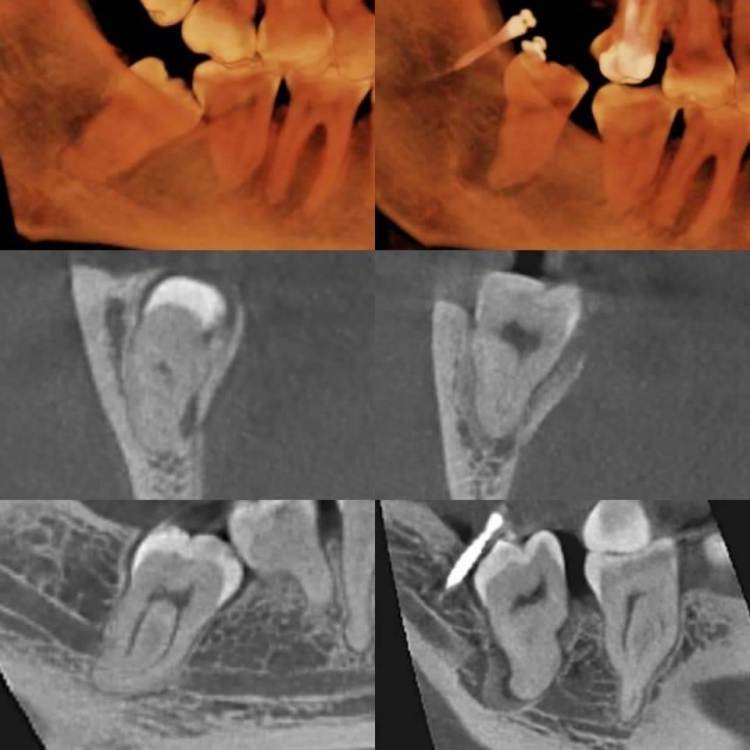

АнтонТЛТ Опубликовано 23 марта, 2021 Поделиться Опубликовано 23 марта, 2021 (изменено) 1 час назад, annda сказал: Антон, все читаю и думаю , как реализовать ортодонтическую экструзию у зуба мудрости? Поделитесь работающей конструкцией... Ставим ортодонтический миниимплантат ретромолярно, на зуб клеится кнопка. Устанавливаем резиновую тягу. Изменено 23 марта, 2021 пользователем АнтонТЛТ 5 2 Ссылка на комментарий

АнтонТЛТ Опубликовано 23 марта, 2021 Поделиться Опубликовано 23 марта, 2021 Это не мой кейс, у автора ушло около 3 месяцев. Обычно для экструзии скорость около 1мм/мес. Ссылка на комментарий

АнтонТЛТ Опубликовано 23 марта, 2021 Поделиться Опубликовано 23 марта, 2021 По факту себестоимость такой экструзии небольшая, если как в этом кейсе использовать отечественный миниимплантат. Ссылка на комментарий